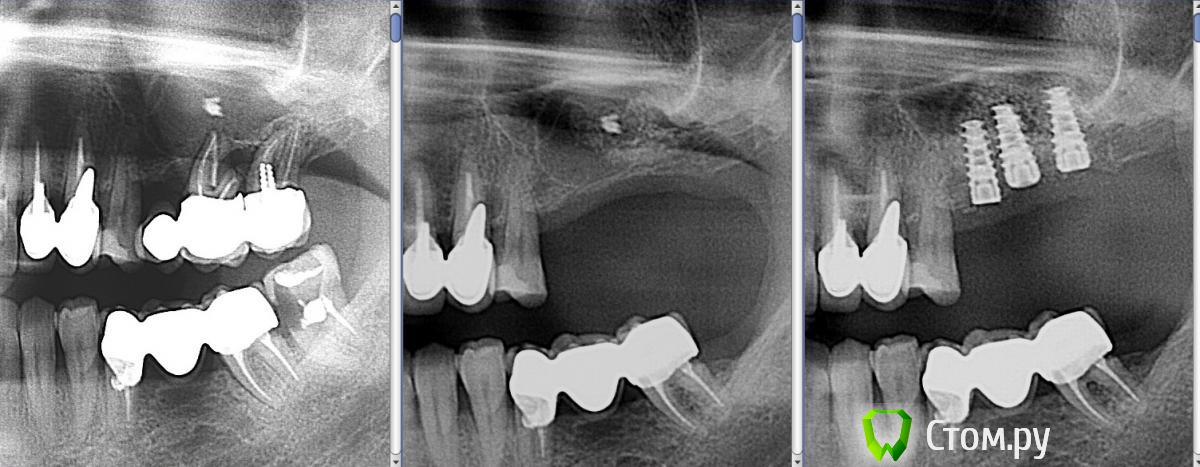

Andex Опубликовано 15 января, 2014 Поделиться Опубликовано 15 января, 2014 Один из первых синусов по открытой методике. Во время работы перфорировал шнайдерову, наложил на место перфорации "special", графт от альфа-био, на окно эволюшн. Прошло 6 месяцев, жалоб как не было с операции, так и нет сейчас. Фото до операции фото после(на сегодня такой вид)Какие ошибки были допущены? Что делать дальше?Мой план - закрытый синус с одномоментной установкой 3х винтов, помолиться, подождать 6 мес и протезировать. Только я считаю-что осложненений нет только у того,кто не работает?Благодарю за обоснованную критику и разумные советы)))) Ссылка на комментарий

Andex Опубликовано 27 января, 2014 Автор Поделиться Опубликовано 27 января, 2014 Кому было интерестно - фото после операции. Сделал сразу все фотки - до и после. Интересует обоснованная критика)) Ссылка на комментарий

red_butler Опубликовано 28 января, 2014 Поделиться Опубликовано 28 января, 2014 ИМХО, близко позиции 25 и 26 по орто, сложно будет размоделировать и гигиену поддерживать...Я тоже такого мнения, 2.6 не стал бы ставить и сделал бы мостом Ссылка на комментарий

Sahan Опубликовано 28 января, 2014 Поделиться Опубликовано 28 января, 2014 С таким близким расположением имплантатов 2.6 будет премоляром. Пользуйтесь шаблонами Ссылка на комментарий

Andex Опубликовано 29 января, 2014 Автор Поделиться Опубликовано 29 января, 2014 тоже интересно Если четно - не знаю на 100% что там. Тк принял решение делать зыкрытый синус. Почитал мнения более опытных и мною уважаемых коллег с форума в этой ветке-что надо делать открытый и ревизию. Когда отслоился - в месте окна после первого синуса очень плотная и толстая кость(по сравнению с с костью до операции), плюс из-за того,что было жалко выбрасывать мембрану-я перекрыл ей не только окно,а еще и крестальную кость, что в итоге дало +1 мм по высоте. На КТ этого видно не было почему то. Все взвесив, сделал закрытый. По ощущениям - графт закладывался намного труднее(туже) чем при классическом закрытом синусе. Всего ушло 1,5 мл на 3 лунки. Импланты 25з - 3.75х10, 26з - 4.2х10, 27з - 4.2х10, торк на всех 40 н/см. Подозреваю,что в пазухе все же фиброзно-графтовая каша. Время покажет праивльно я поступил или нет, или же надо было прислушаться к советам. Но это мое решение, и отвечать за него тоже буду я) 1 Ссылка на комментарий